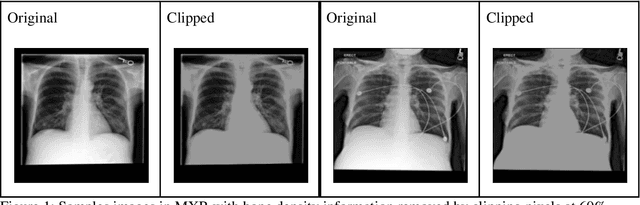

Abstract:Background: In medical imaging, prior studies have demonstrated disparate AI performance by race, yet there is no known correlation for race on medical imaging that would be obvious to the human expert interpreting the images. Methods: Using private and public datasets we evaluate: A) performance quantification of deep learning models to detect race from medical images, including the ability of these models to generalize to external environments and across multiple imaging modalities, B) assessment of possible confounding anatomic and phenotype population features, such as disease distribution and body habitus as predictors of race, and C) investigation into the underlying mechanism by which AI models can recognize race. Findings: Standard deep learning models can be trained to predict race from medical images with high performance across multiple imaging modalities. Our findings hold under external validation conditions, as well as when models are optimized to perform clinically motivated tasks. We demonstrate this detection is not due to trivial proxies or imaging-related surrogate covariates for race, such as underlying disease distribution. Finally, we show that performance persists over all anatomical regions and frequency spectrum of the images suggesting that mitigation efforts will be challenging and demand further study. Interpretation: We emphasize that model ability to predict self-reported race is itself not the issue of importance. However, our findings that AI can trivially predict self-reported race -- even from corrupted, cropped, and noised medical images -- in a setting where clinical experts cannot, creates an enormous risk for all model deployments in medical imaging: if an AI model secretly used its knowledge of self-reported race to misclassify all Black patients, radiologists would not be able to tell using the same data the model has access to.